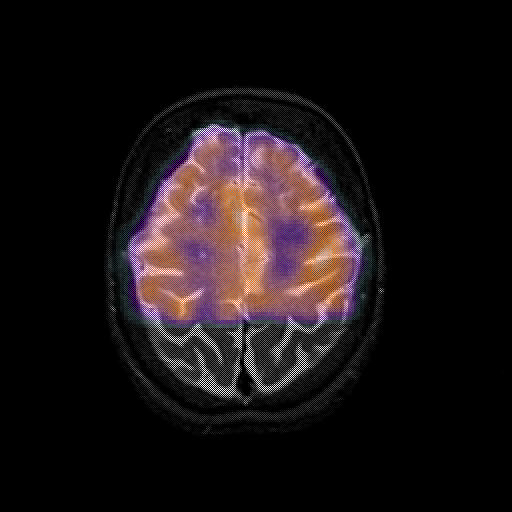

overlay 1: Slice 41

Slice 41

MRCBFCBF with

T1PDT2T1PDT2